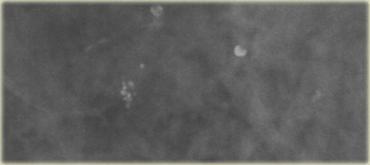

Các hình ảnh cho thấy hình dạng khác nhau trên tư thế chếch so với tư thế bên trong-ngoài.

Trên tư thế bên trong-ngoài có hiện tượng lắng đọng canxi thành lớp.

Trên hình chụp tư thế đầu-đuôi, các vôi hóa có dạng tròn, mờ và bờ không rõ nét.

Trên tư thế bên trong-ngoài, các vôi hóa có dạng hình bán nguyệt, hình lưỡi liềm như tách trà.